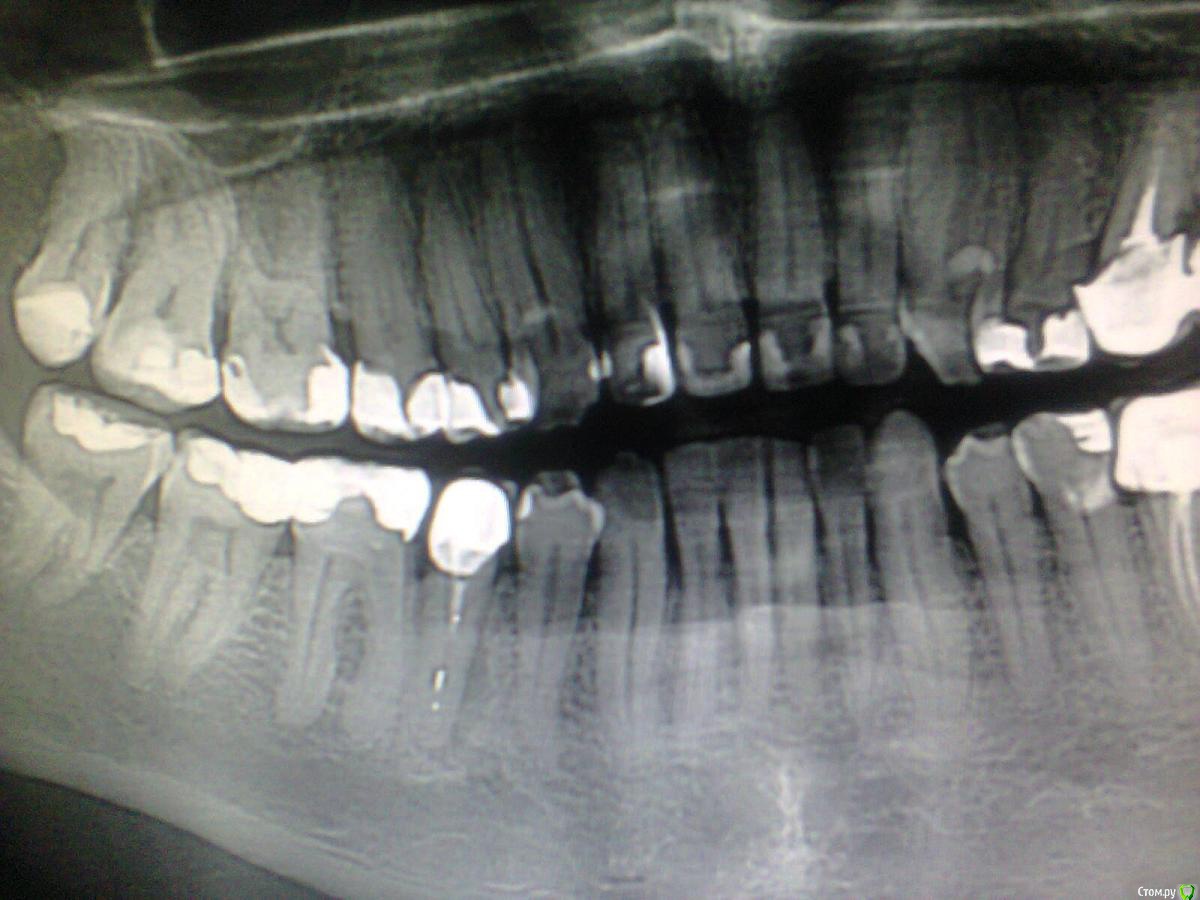

St. Опубликовано 27 июля, 2015 Автор Поделиться Опубликовано 27 июля, 2015 Как думаете, в 45 трещина или латераль? А то слишком форма разряжения подозрительная...Зуб лечился давно, не беспокоит. Обнаружили на орто. Ссылка на комментарий

Bratok Опубликовано 27 июля, 2015 Поделиться Опубликовано 27 июля, 2015 Как думаете, в 45 трещина или латераль? А то слишком форма разряжения подозрительная...Зуб лечился давно, не беспокоит. Обнаружили на орто.Обычно очаги такой локализации наводят на мысль о трещине, может стоит сделать кт? Ссылка на комментарий

NinaK Опубликовано 28 июля, 2015 Поделиться Опубликовано 28 июля, 2015 Обычно очаги такой локализации наводят на мысль о трещине, может стоит сделать кт?Ну и плюс оптика, ибо трещины, к сожалению, не всегда видны даже на КТ... Ссылка на комментарий

St. Опубликовано 28 июля, 2015 Автор Поделиться Опубликовано 28 июля, 2015 На кт отправлен сразу же.Посмотрим. Просто форма разряжения.... Думаю, что пациенту перед вмешательством рассказывать, и к чему готовить, поэтому интересно мнение со стороны.Видимо готовить к худшему Ссылка на комментарий

Donny Опубликовано 29 июля, 2015 Поделиться Опубликовано 29 июля, 2015 Возможно все таки латераль учитывая качество пломбирования, кт не помешает в целом, а в конкретном зубе только вскрытие покажет. Ссылка на комментарий